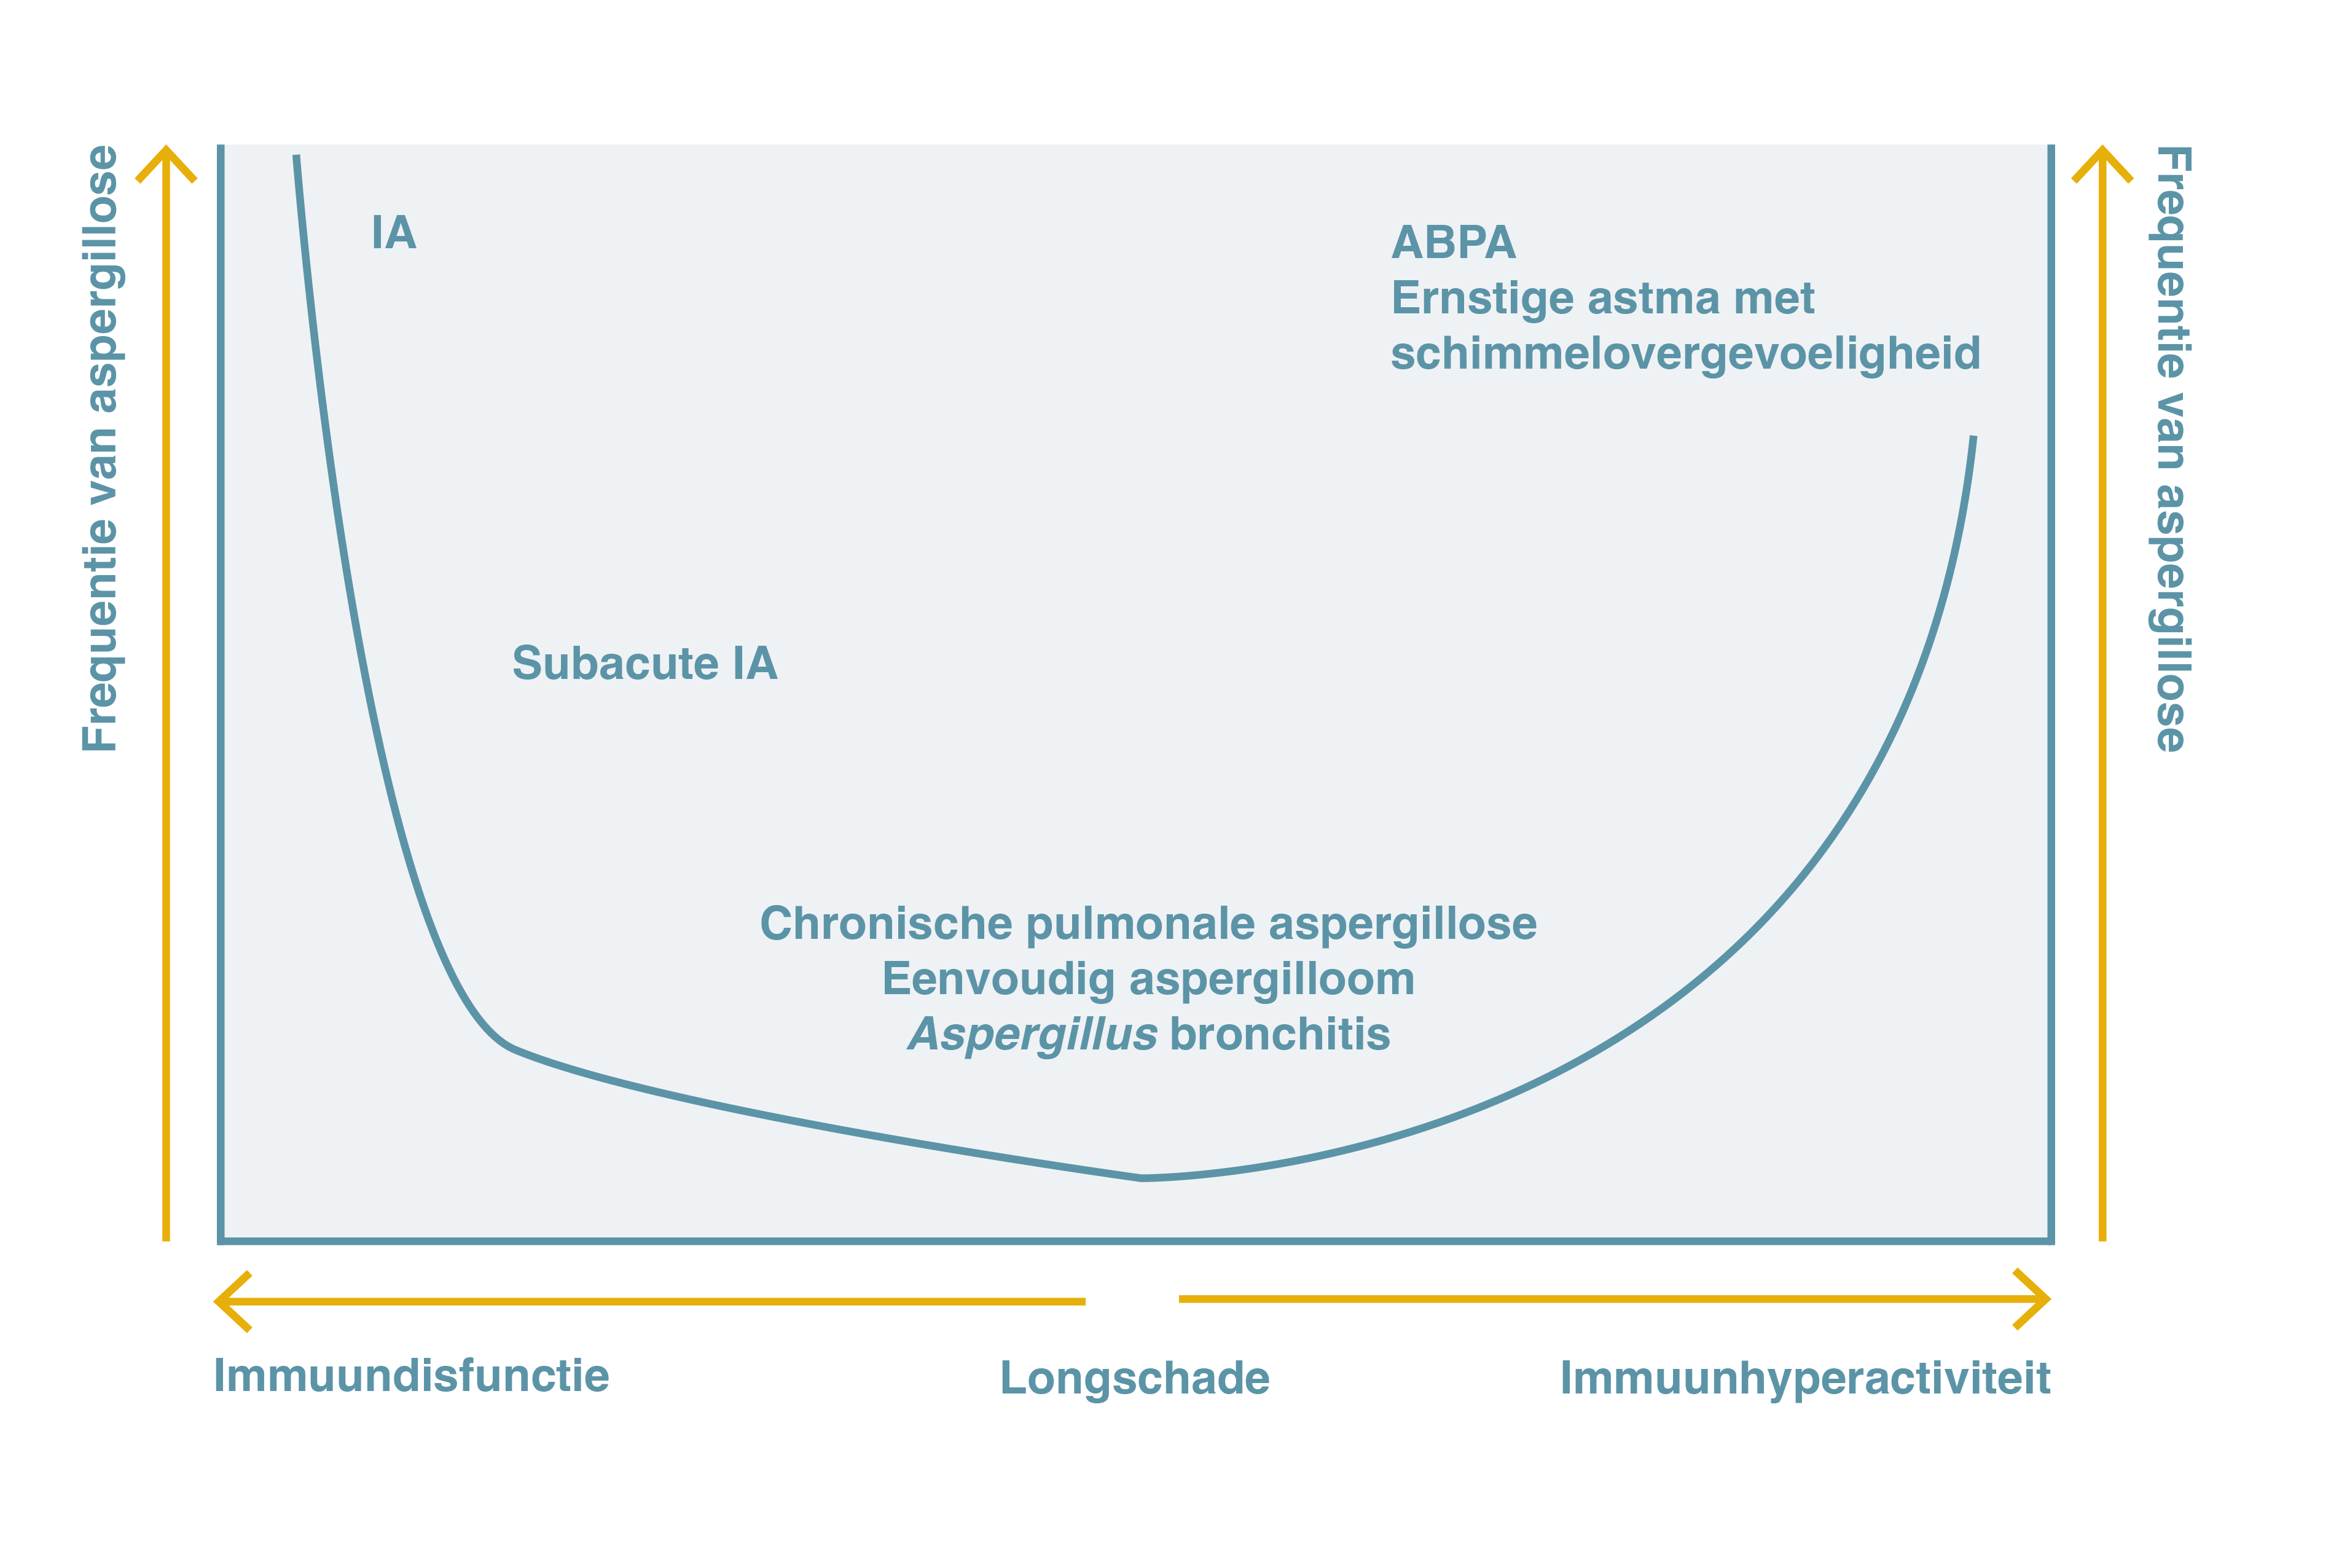

In figuur 1 staan de belangrijkste ziektebeelden die door Aspergillus veroorzaakt worden schematisch afgebeeld, in functie van de respons van het immuunsysteem.

Figuur 1. Het klinische spectrum van Pulmonale Aspergillose Overgenomen en bewerkt van Kosmidis C et al. 20159

ABPA=Allergische bronchopulmonale aspergillose